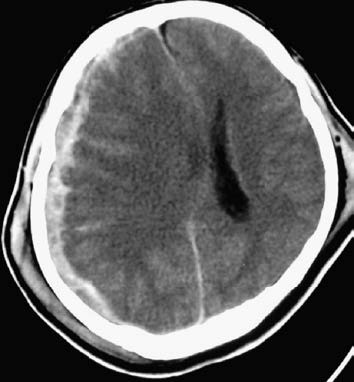

A history of head trauma followed by immediate or progressively worsening consciousness impairment, or a lucid interval accompanied by symptoms of increased intracranial pressure, often suggests acute or subacute subdural hematoma. CT imaging confirms the diagnosis; acute or subacute subdural hematomas appear as crescent-shaped hyperdense, mixed-density, or isodense lesions between the brain surface and the skull, often accompanied by brain contusions and cerebral compression.

Figure 1 Acute subdural hematoma (CT, right frontoparietal lobe)